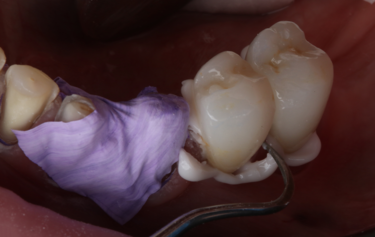

Figure 13: Gingival retraction on final preparations

A 6-week period was allowed to pass to give the gingiva time to heal and settle around the milled temporary restorations. On review the patient was very happy with the aesthetics of her smile but wanted the teeth a little whiter in colour. The form and function of the teeth was balanced, and the patient was comfortable at the new OVD. The temporary restorations were easily removed, followed by final refinement of the tooth preparations, and then retraction with PTFE placed into the sulcus ahead of a Trios intra-oral digital scan of the final preparations (Fig. 13). The posterior bite relationship of the prepared teeth was digitally recorded over the premolar area by using the anterior upper and lower 4 crowns to support the patient in the correct centric relation position.

On the day of cementation, the temporary milled restorations were once again removed, and the exquisite gingival health observed (Fig. 18). By using the milled Telio-CAD temporaries the patient has far better control over their oral health around the restorations and the gingival health is always far superior to that when using a conventional ‘shrink-wrap’ technique. The new restorations were tried onto the teeth and the fit and aesthetics assessed. Figure 19 shows the exact replication of shape and size between the temporary (bottom) and final (top) restorations at this try-in stage. The teeth were prepared for bonding following standard protocol of air-abrasion to remove any biofilm and to create enhanced micromechanical retention, followed by a 2% chlorhexidine scrub.